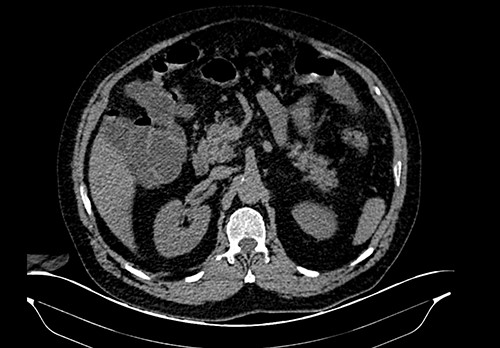

On the CT, the whole extent of the bowel was dilated; however, no free liquid, air or masses were found (Fig. 1). Nevertheless, the patient’s abdominal pain and distention worsened. Due to this, surgical consultation was needed, and after obtaining consent, surgery was decided as intestinal ischemia was among the differential diagnosis.